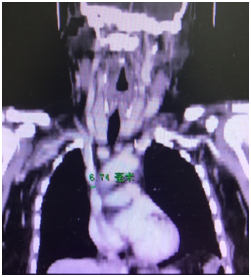

患者来到天津医院肾内科,立刻受到了杨定位主任的高度重视,杨主任和科室血管通路专管主任王维秀立刻就患者的血管条件进行评估,通过联系放射科何岸伟主任,立即为患者完善双侧颈内静脉、无名静脉、上腔静脉的CT血管检查。通过造影剂显影,直观的观察到右侧无名静脉血管壁钙化及上腔静脉狭窄畸形。患者最狭窄处上腔静脉直径仅6.74mm,而常规颈内静脉长期透析导管直径5mm,置管后上腔静脉综合征、颜面双上肢水肿发生率极高,且置管后血栓形成发生率高,导管使用寿命不长。